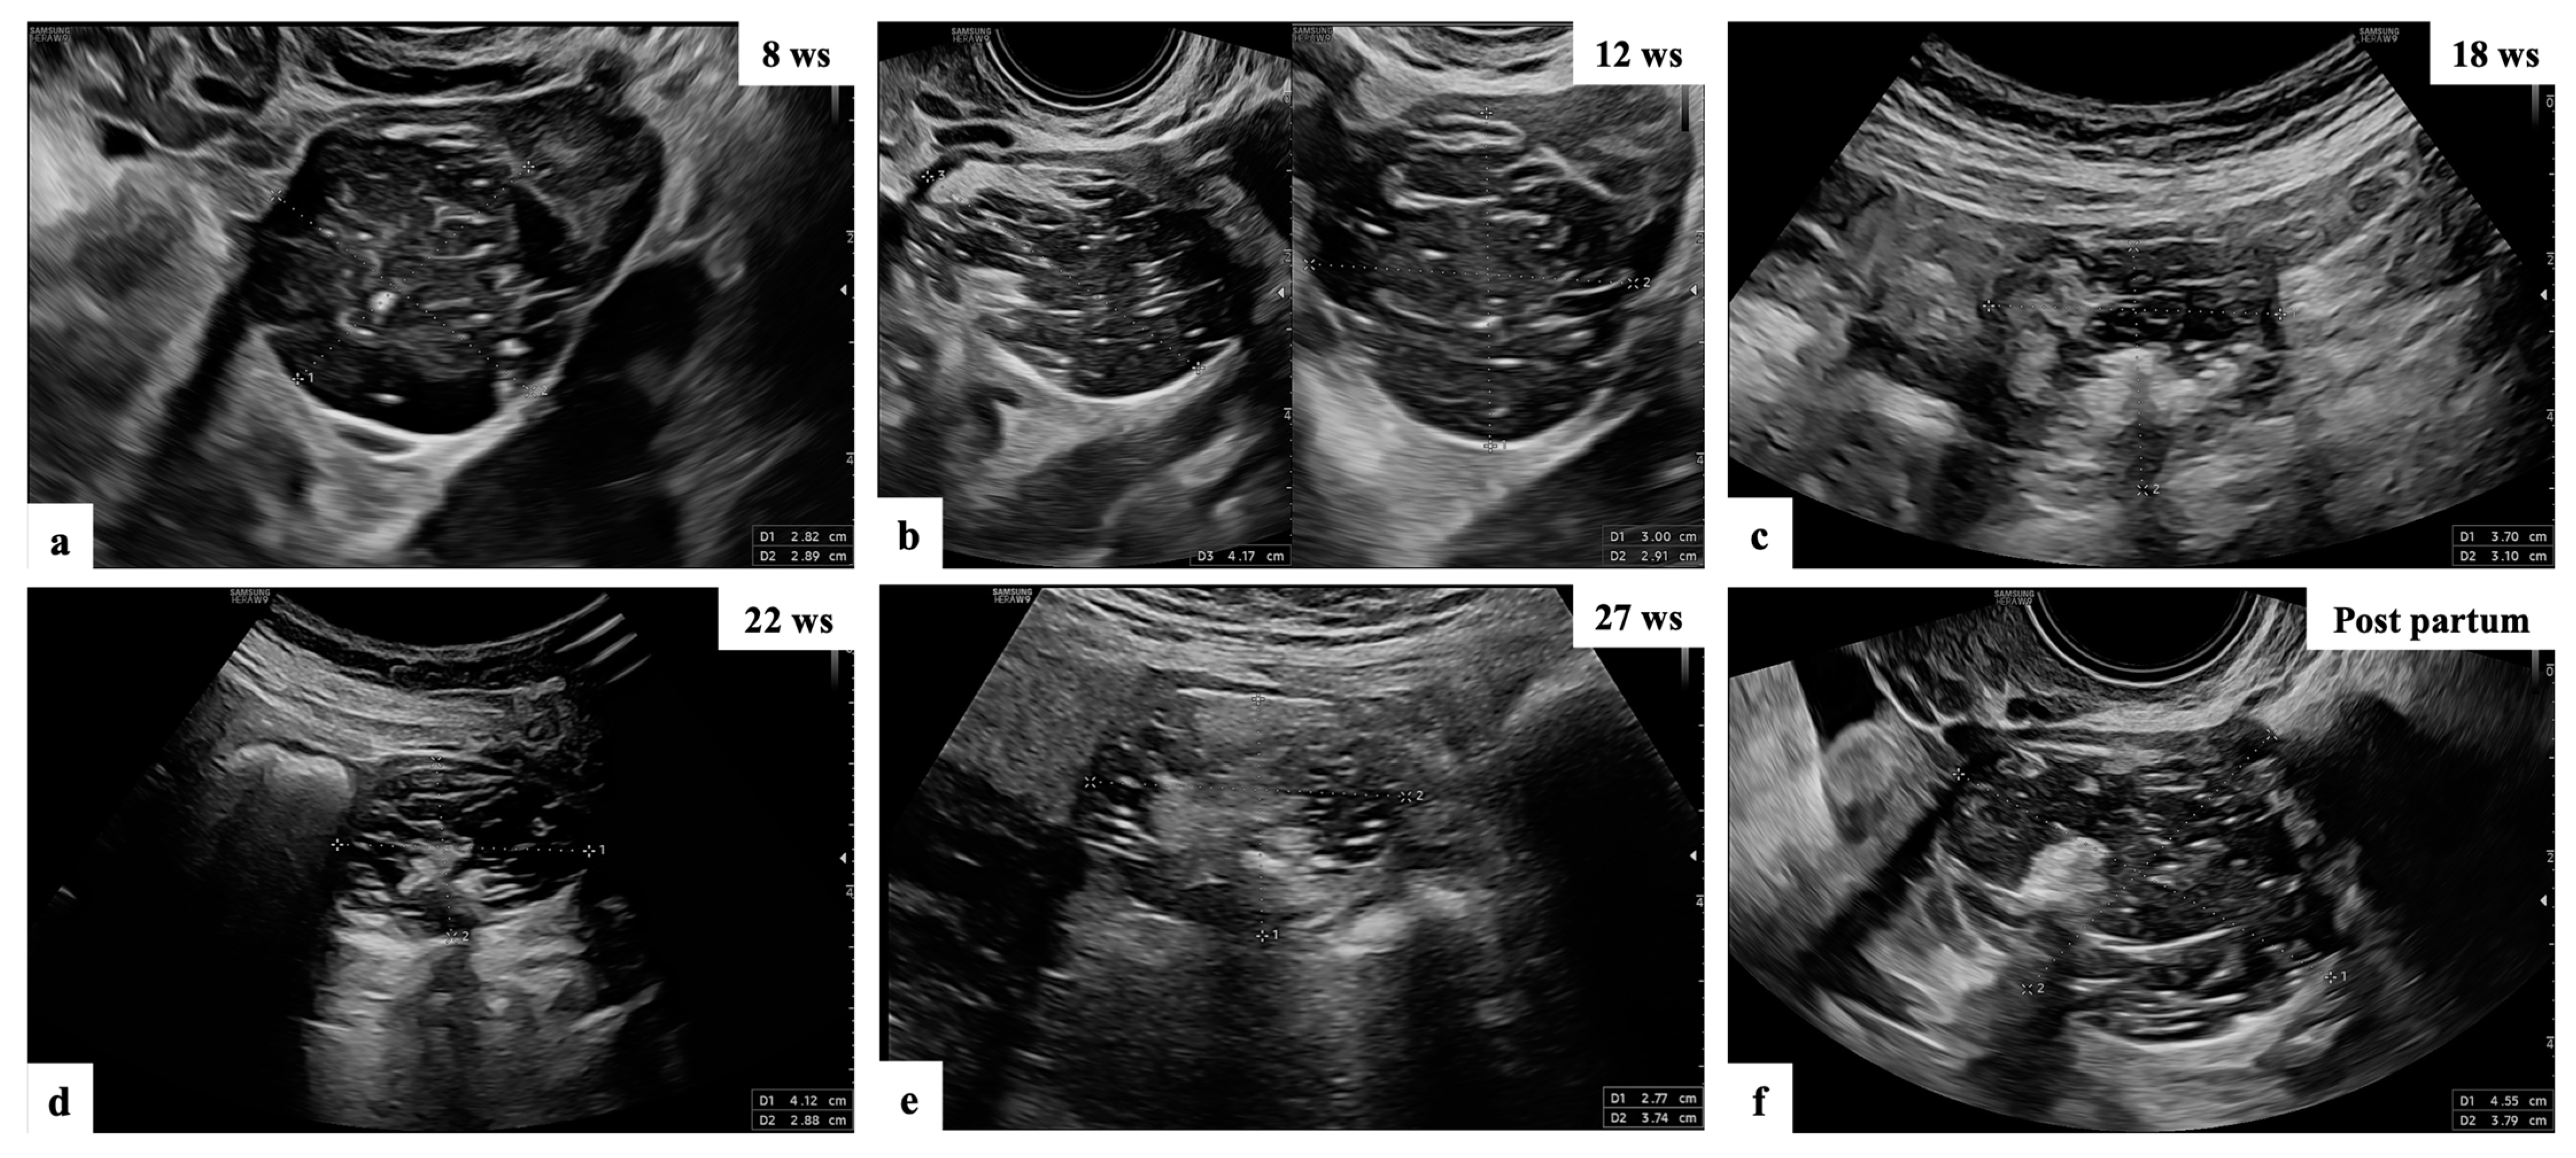

- Mascilini, F.; Moruzzi, C.; Giansiracusa, C.; Guastafierro, F.; Savelli, L.; De Meis, L.; Epstein, E.; Timor-Tritsch, I.E.; Mailath-Pokorny, M.; Ercoli, A.; et al. Imaging in gynecological disease. 10: Clinical and ultrasound characteristics of decidualized endometriomas surgically removed during pregnancy. Ultrasound Obstet. Gynecol. 2014, 44, 354–360. [Google Scholar] [CrossRef]

- Pateman, K.; Moro, F.; Mavrelos, D.; Foo, X.; Hoo, W.L.; Jurkovic, D. Natural history of ovarian endometrioma in pregnancy. BMC Women’s Health 2014, 14, 128. [Google Scholar] [CrossRef]